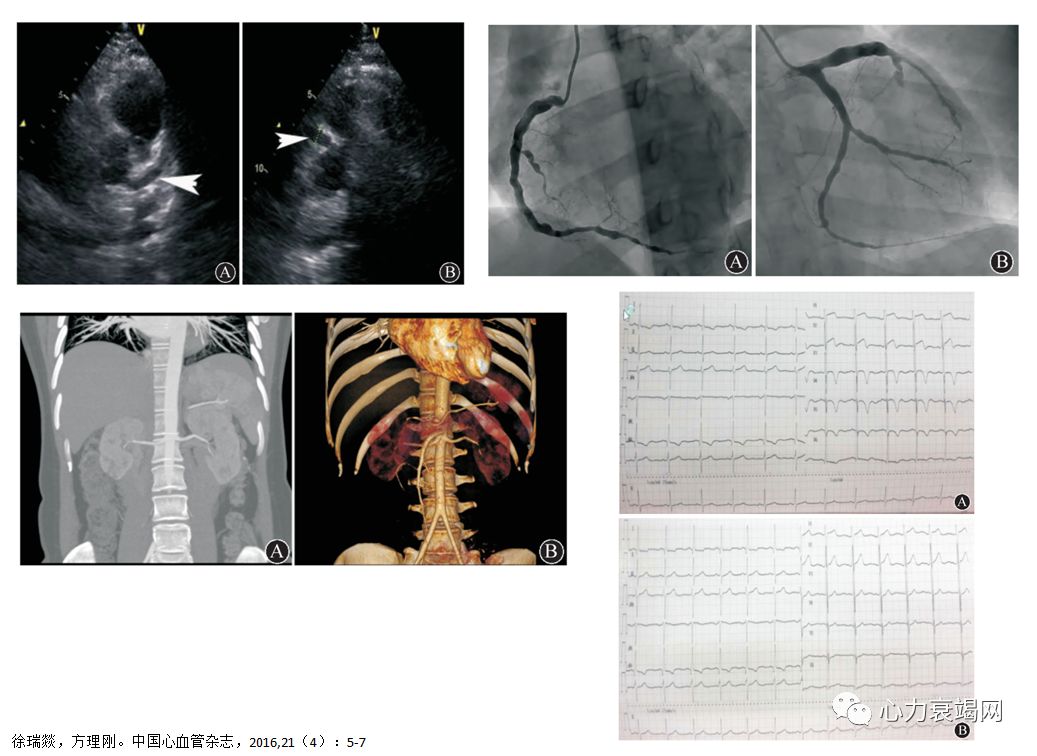

女,15岁

双下肢红斑1年,全身乏力1月,喘憋咯血2周

BP:(左上肢)161/114mmHg,(右上肢)140/?mmHg,下肢血压测不出

NT-Pro-BNP 12653pg/ml

右侧肱动脉近心段局限性重度狭窄,

双侧股总、股浅动脉狭窄

治疗前

甲强龙40mg qdivgtt,CTX0.4g/w

四联抗结核:

- 异烟肼0.3g qd+利福平0.45g qd+吡嗪酰胺0.5g tid+乙胺丁醇0.75g qd

补钙、抑酸、保肝

胸闷明显好转、无咯血,可以平卧,平地活动不受限

限水每日1500ml、利尿(每日速尿60mgiv+螺内酯20mgqdpo)、扩血管(硝酸甘油泵入25mg/h)、补充电解质。

卡维地洛6.25mg Q12h,开博通6.25mg Q8h。

2个月后

激素及抗心衰治疗后